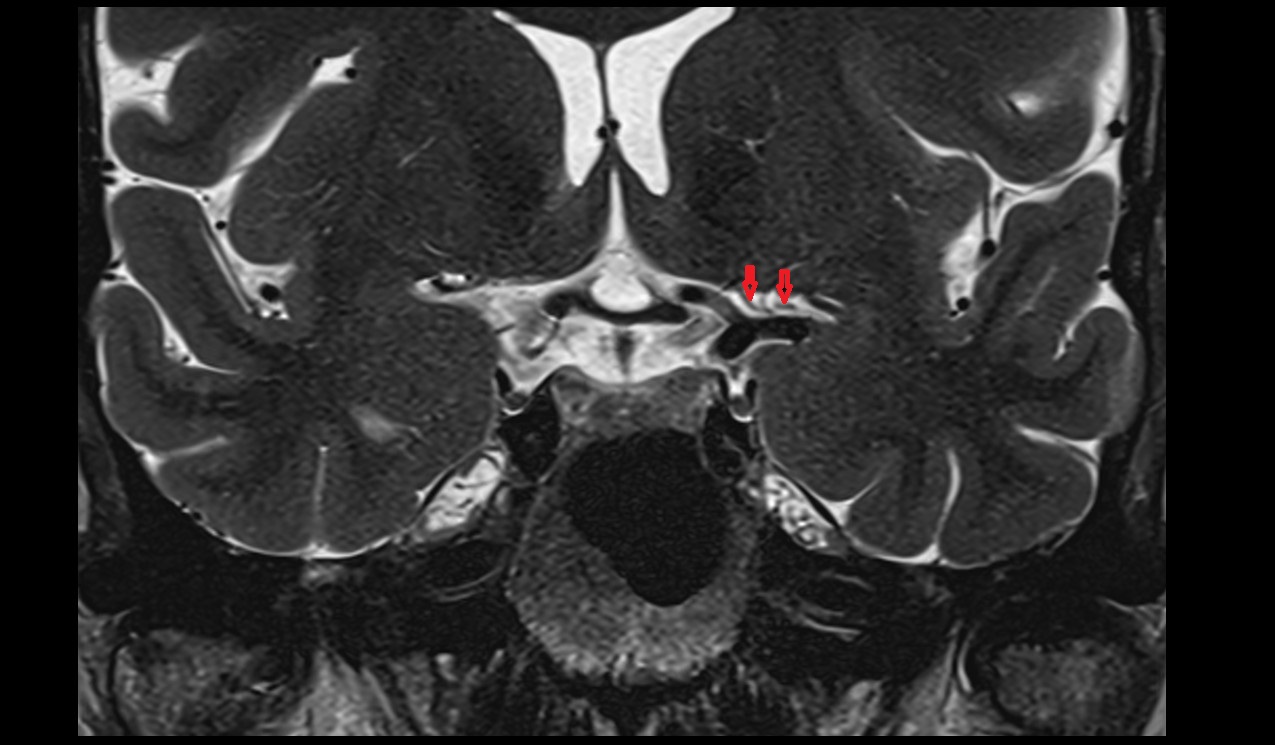

- Hippocampus

- Body of hippocampus

- Head of hippocampus

- Tail of hippocampus